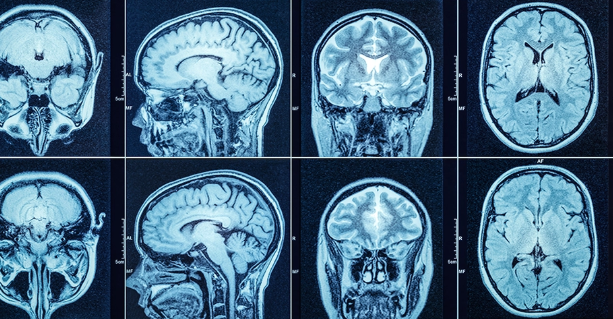

머리 CT 검사는 여러 상황에서 필요하다는 진단이 내려지곤 합니다. 일반적으로 의사가 이 검사를 권유하는 데는 다음과 같은 증상이 있을 수 있습니다.

CT는 일반 촬영과 조영제를 활용한 촬영으로 나뉘며, 조영제를 사용하는 경우 비용이 상승합니다. 조영제는 혈관을 통해 뇌의 혈류 흐름 등을 더 정밀하게 확인하기 위해 사용됩니다.

보통 10~20분 내외로 촬영이 완료되며, 비교적 비용이 저렴합니다. 이 경우 촬영 자체만으로는 충분한 정보를 얻기 어려운 경우도 있으나, 초기 확인 목적에는 적합하다는 설명을 들었습니다.

조영제 CT

검사 전 조영제를 주사하며, 고해상도 촬영이 가능하지만 비용은 5만~10만 원 이상 추가됩니다. 조영제를 사용할 경우 사전 금식이 필요하거나 부작용 안내를 받기도 하므로, 절차가 조금 더 까다롭습니다.